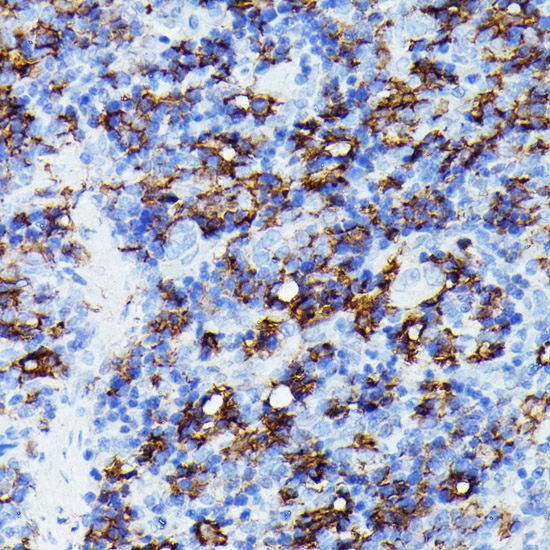

DescriptionIba1 Polyclonal Antibody. Unconjugated. Raised in: Rabbit.

ImmunogenRecombinant fusion protein containing a sequence corresponding to amino acids 1-147 of human Iba1 (NP_001614.3).

ApplicationWB, IHC, IF; Recommended dilution: WB 1:500 - 1:2000, IHC 1:50 - 1:100, IF 1:50 - 1:100